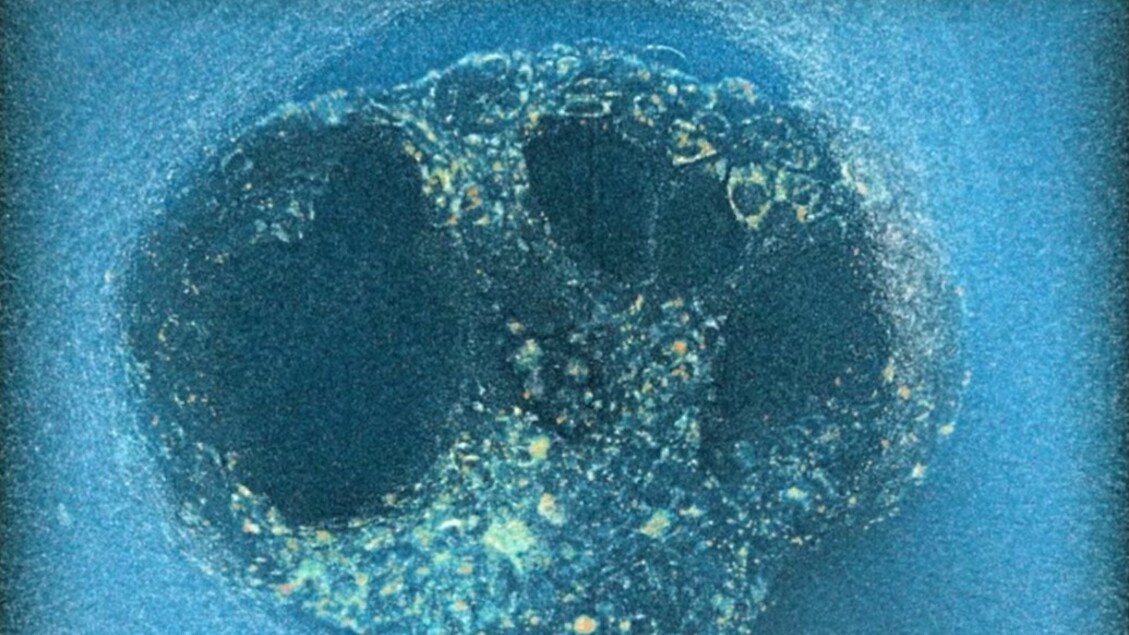

Il team guidato dall’ingegnere biologico Samuel Ojosnegros ha sviluppato una matrice gelatinosa che riproduce le caratteristiche dei tessuti uterini, composta principalmente da proteine come il collagene. All’interno di questa struttura sono stati inseriti embrioni umani donati da coppie sottoposte a fecondazione in vitro. Le immagini ottenute mostrano come gli embrioni non si limitino ad aderire superficialmente alla matrice: al contrario penetrano attivamente e profondamente, creando una cavità che facilita l’ancoraggio e la crescita successiva.

Questa osservazione dinamica rappresenta un passo avanti rispetto agli studi precedenti condotti su modelli murini, nei quali l’invasione della matrice uterina risultava molto più superficiale. L’esperimento dimostra quindi che l’impianto umano comporta un’interazione meccanica più complessa e aggressiva con il tessuto materno rispetto a quanto ipotizzato finora.